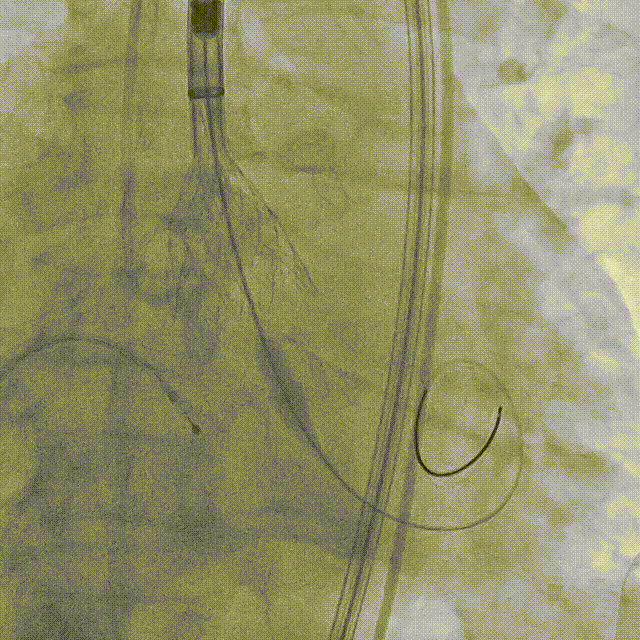

5. 植入26mm Evolut PRO瓣膜

瓣膜释放到2/3的位置(手柄上有触觉提示)

瓣膜释放到80%并造影评估深度合适(少量反流,瓣膜形态椭圆)

左冠切线位造影评估冠脉风险(左冠血流灌注良好)

22mm球囊后扩张(瓣膜形态更佳)

最终造影(反流微量)

精准释放角度:左右冠窦重叠。

左右窦重叠角度可以清楚显示无冠窦,维持冠窦平面对齐,拉长左室流出道的视图,减少或去除医生的视差,以精准评估瓣膜植入深度。